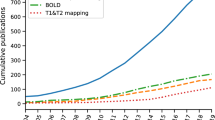

It is interesting to consider exactly how much clinical and preclinical research activity in cardiac and renal MRI there has been, and how it has grown over the years. Using publications listed in PubMed as an indicator, we performed tailored searches with PubMed’s Medical Subject Headings (MeSH) to obtain lists of literature on renal/cardiac MRI in humans/animals (Fig. 2, upper panels). Additionally we used PubMed’s MeSH Major Topic to restrict the searches to papers that focus on renal/cardiac MRI while excluding articles that only mention these terms but have another focus (Fig. 2, lower panels) (see Note 1).

The number of publications in both fields has grown considerably over the years, but at very different rates. Around 1000 cardiac MRI papers per year were published during 2014–2018; the equivalent number for renal MRI papers was only around 200. After restricting the search to papers with a main focus on MRI of the kidney/heart the number of papers per year were 400 and 70, respectively. In other words, a lot more research activity in renal MRI is needed. From the number of publications one can deduce that there is considerably more clinical research than preclinical research in renal MRI. Conceivably, this is partially due to the more limited availability of preclinical MRI systems. However, preclinical renal MRI has recently seen a rapid increase to 37% of all renal MRI publications. This highlights the importance of animal research in renal MRI, considering that only 5% of cardiac MRI papers are preclinical (as of 2018).

The renal MRI research community is still rather small. While a recent SCMR meeting attracted more than 1900 attendees [7], international meetings on renal MRI have had approximately 150–200 attendees [8, 9]. Around 200 experts in renal MRI from 30 countries are part of PARENCHIMA (renalmri.org), a community-driven Action in the COST program of the European Union, with the aim to improve the reproducibility and standardization of renal MRI biomarkers. In fact, the number of research groups active in preclinical renal MRI is only 1/5 of those active in clinical renal MRI (see Note 2). One important conclusion from this is that accelerating the development of renal MRI will require more researchers and institutions to enter the field. We may ask ourselves, “What hurdles are slowing down progress and impeding clinical translation?”